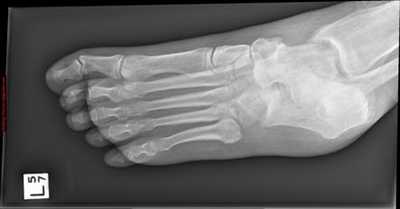

Для диагностики состояния стопы применяют рентгенологические методы, КТ и МРТ. Рентгенограмму делают в нескольких проекциях. На рентгене видны кости стопы и голеностопного сустава, плотность костей, а также состояние свода стопы. С помощью рентгенологических методов определяют переломы костей, деформации пальцев, дегенеративно-дистрофические заболевания суставов.

![]() | Рис. 13. Рентгенограмма стопы в состоянии свободного виса. При сгибании в голеностопном суставе продольный свод стопы увеличен |

![]() | Рис. 14. Рентгенограмма стопы и голеностопа взрослого человека в разных проекциях. Видны кости, образующие свод стопы |